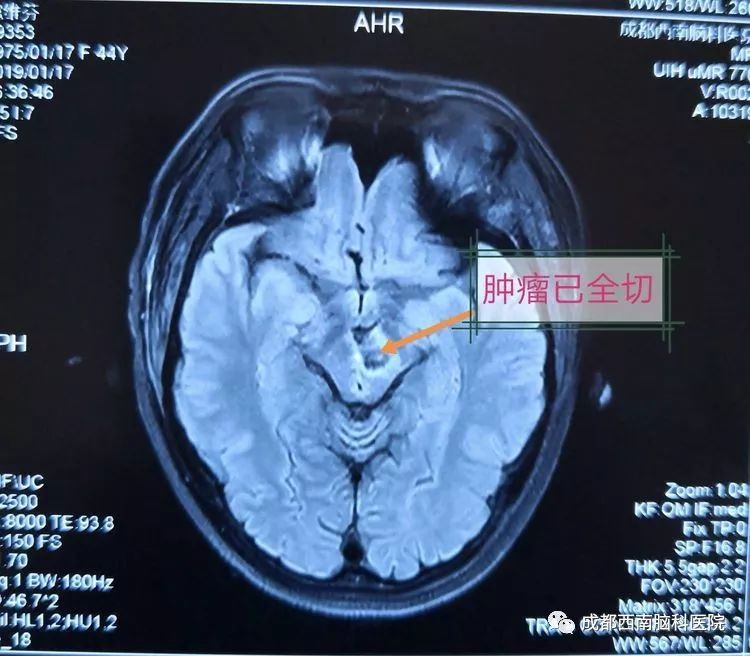

术后复查MRI显示已全部切除

术后当晚,医生检查发现,患者回答问题准确、切题,原有的颅神经麻痹、动眼神经麻痹没有加重,术前担心的肢体瘫痪症状也没有出现,理解力、反应力、记忆力、语言功能正常。术后第二天,患者视物清晰,四肢运动功能、感觉功能完好。